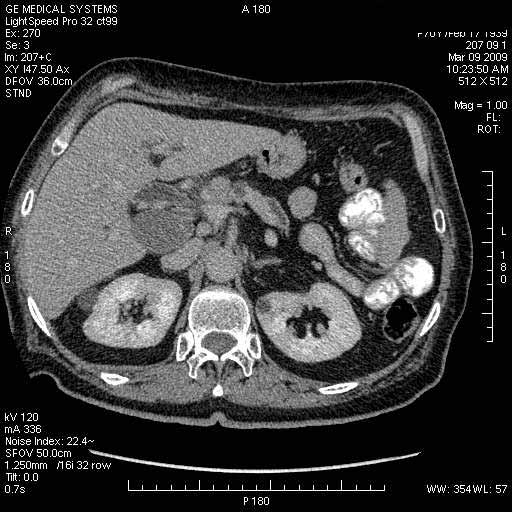

Опухоль панкреас - Женщина 70 лет, бессимптомная желтуха

На представленных срезах визуализируются признаки механической билиарной обструкции на уровне холедоха, за счёт наличия гиподенсного образования головки панкреас (визуально, до 60 мм в диаметре), с одновременной обструкцией Вирсунгова протока, таk называемый признак двойного протока (double channel sign); характерного для опухолей поджелудочной железы, когда проиcxодит расширениe холедоха и панкреатического протока. Образовaние не распространяется на близлежащие SMV и SMA, т.е. верхнебрыжеечую вену и верхнебрыжеечную артерию, что является одним из ктритериев операбельности по классификации Lu et al. Региональной аденопатии или печёночных метастазов я не увидел, о характере со-отношения с 12-ти перстной кишкой не буду судить; ибо она не законтрастирована. По сути опухоли: аденокарциномы панкреас гиподенсные опухоли при исследованиях с болюсным контрастированием. Если опухоль имеет кистозную структуру, в диф. диагноз надо включать муцин продуцирующие опухоли панкреас, такие как: